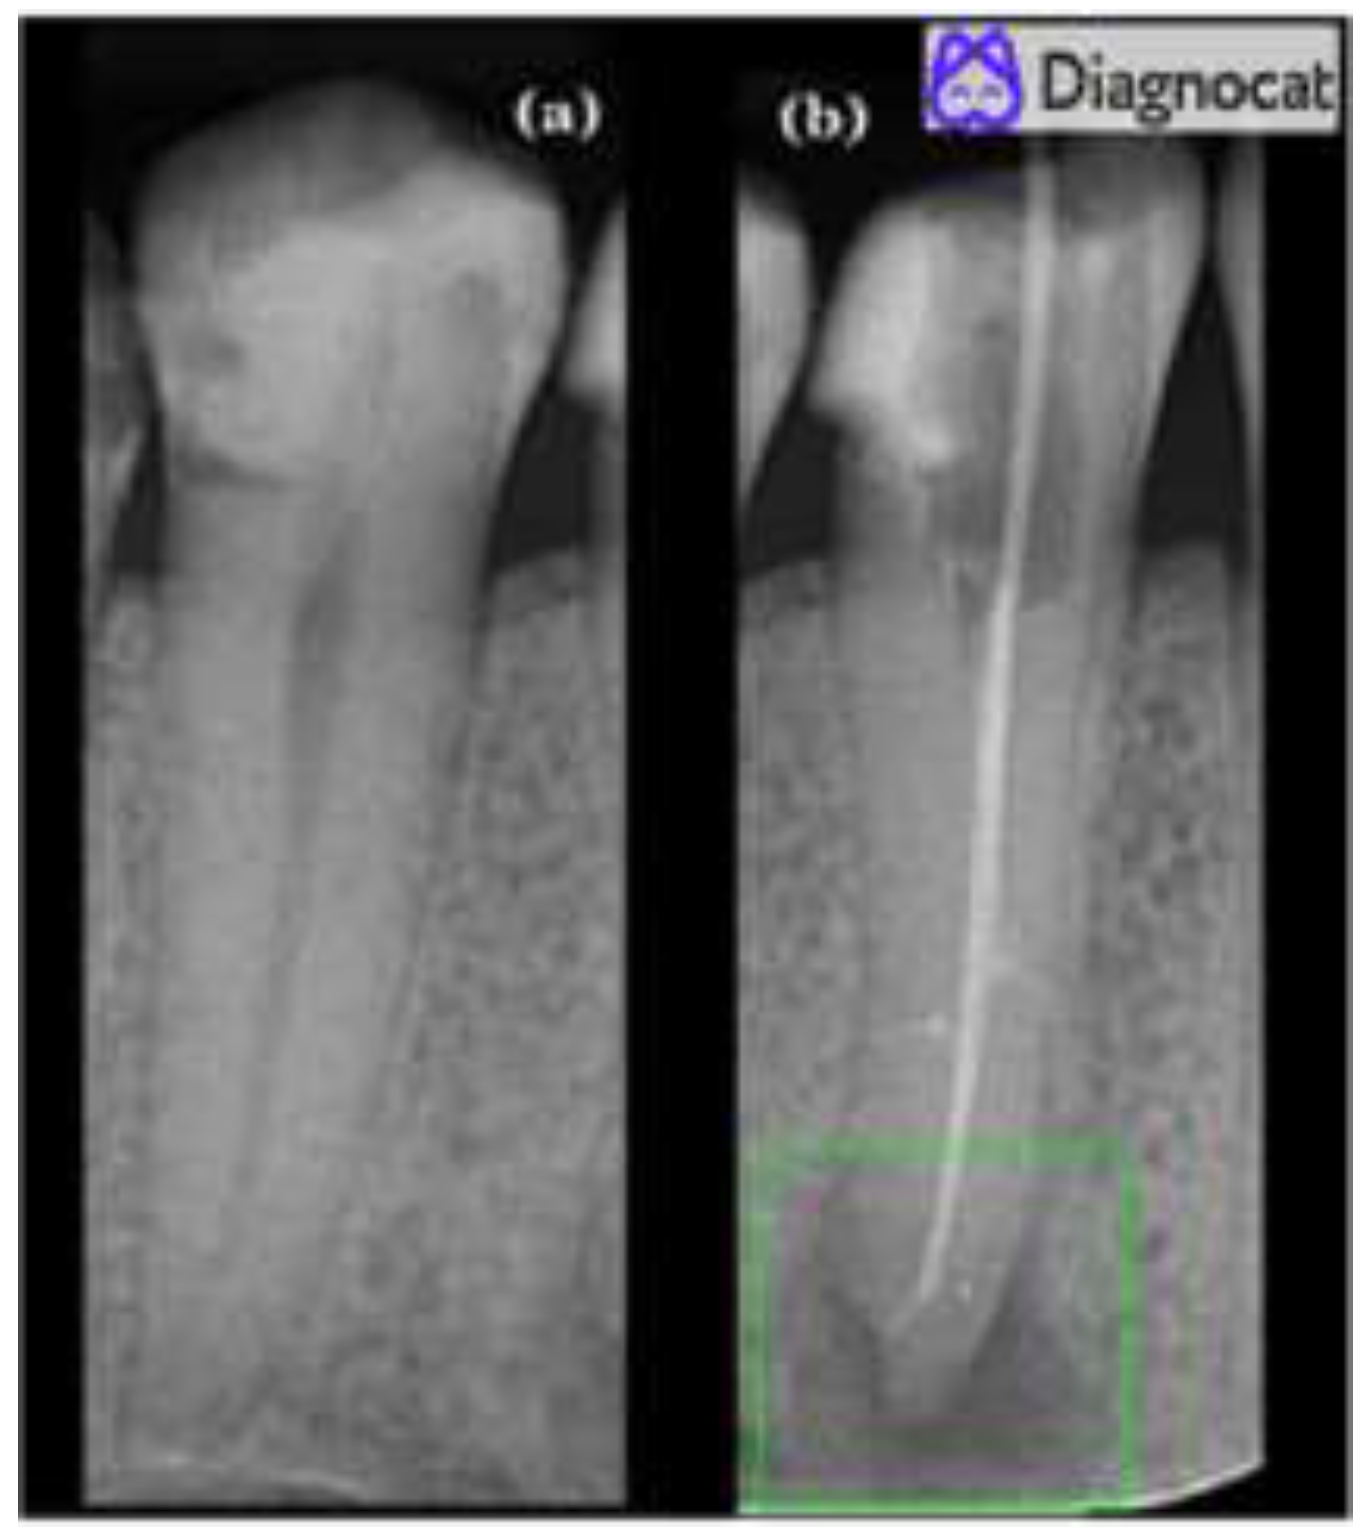

3.3. Automated Evaluation

- Twelve true positives (TP) (teeth with apical periodontitis, unhealthy);

- One false positive (FP) (tooth with no signs of apical periodontitis was classified as unhealthy, over-diagnosed by the tool);

- Forty-six true negatives (TN) (healthy teeth, no signs of any apical periodontitis);

- One false negative (FN) (misdiagnosed by the tool; a tooth with apical periodontitis was classified as a healthy tooth).